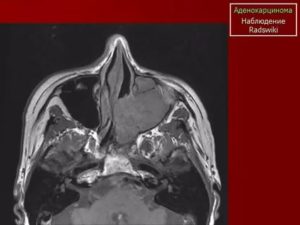

- Еще одна из распространенных форм — аденокарцинома. При этом заболевание начинается с аденоматозных клеток, которые находятся в носовой полости и производят слизь. Аденокарцинома сопровождается болезненными ощущениями в области глазниц и скованностью в нижней челюсти. Что влечет за собой ухудшение зрения и сложности при открытии рта.